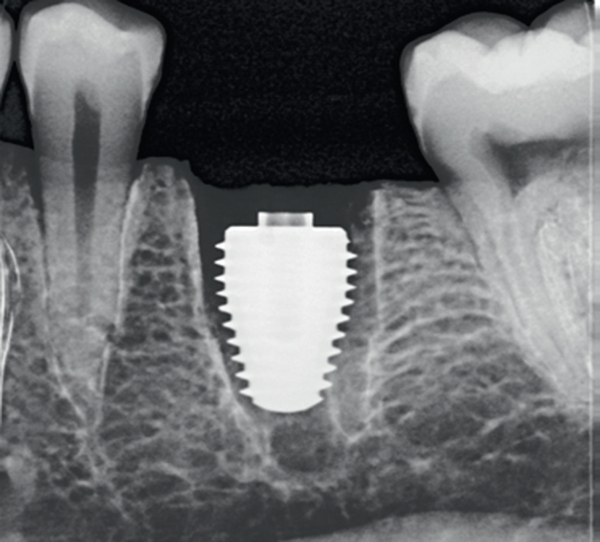

UltraWideDiameter Implants Gaining Favor for Immediate

UltraWideDiameter Implants Gaining Favor for Immediate from www.aegisdentalnetwork.com